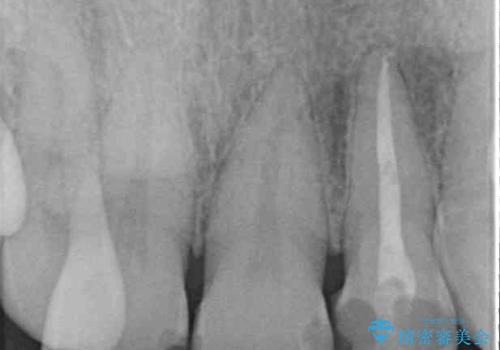

レントゲン写真より、歯根の炎症が認められなかったため、ファイバーコアによる土台築製後、オールセラミッククラウンにて補綴することとしました。